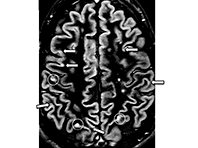

Исследование 255 человек с прогрессивным рассеянным склерозом показало: ибудиласт способен тормозить процесс развития атрофии мозга, передают Национальные институты здравоохранения США. Из побочных эффектов наблюдались головные боли и проблемы с пищеварением. Ежедневно добровольцы принимали до 10 капсул препарата или плацебо в течение 96 недель. Каждые полгода они проходили сканирования мозга для контроля. Атрофия была в обеих…